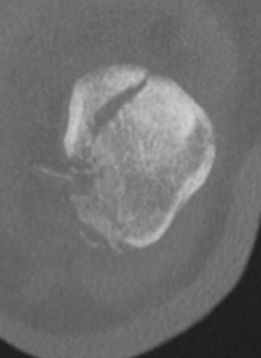

CT

Osteochondral fracture of the lateral femoral condyle

Large osteochondral fracture medial facet patella

Large osteochondral fracture lateral femoral condyle